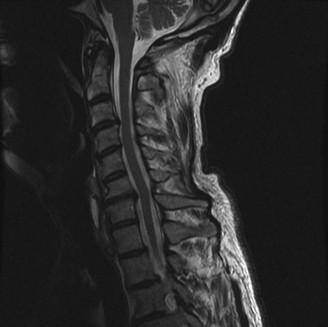

Recognize surgical and nonsurgical indications for a thoracic lymphoma? Definitively manage a thoracic lymphoma? CASE 13 A 23-year-old man was involved in a high-speed motor vehicle accident. On presentation to the trauma bay, his chief complaint was neck pain. Physical examination demonstrated that he was neurologically intact. Images of the cervical spine are shown in Figure 1–19A–B. Full workup demonstrated no other injuries.

Figure 1–19 A–B

The correct answer is (B). The imaging clearly demonstrates a Hangman’s fracture, also known as a C2 traumatic spondylolisthesis. The hallmark of this injury is a fracture through the pars interarticularis of C2, which effectively dissociates the anterior elements from the posterior arch and facet joints. A Jefferson fracture refers to C1 ring fractures that can have varying degrees of lateral displacement. There is no evidence of vertebral body comminution with posterior vertebral body involvement, which would be characteristic of a burst fracture. While some Hangman’s fractures can be associated with facet dislocation, there is no evidence of this on the imaging.

The correct answer is (B). Type I fractures have minimal horizontal displacement, no angulation, and the C2–3 disc remains intact. Type II fractures are both displaced and angulated, presumably hinging around the anterior longitudinal ligament. Importantly, these fractures reduce with longitudinal traction. Type IIA fractures have minimal horizontal displacement but are significantly angulated. It is presumed that the anterior fragment rotates in place, most likely disrupting the anterior longitudinal ligament. These injuries are worsened by traction and reduced with axial compression. Type III fractures have bilateral C2–3 facet dislocations.

The correct answer is (B). While type I fractures can be treated immediately in a hard collar, type II fractures are best treated initially with traction to achieve fracture reduction. After a short period of traction, the patient should be placed in a halo vest to allow mobilization. As indicated above, type IIA fractures should not be placed in traction; patients should be placed in a halo vest with some axial compression applied. Type III fractures require surgical reduction of the facet dislocation and internal stabilization. Objectives: Did you learn...? Identify a Hangman’s fracture based on imaging? Understand the classification of Hangman’s fractures?